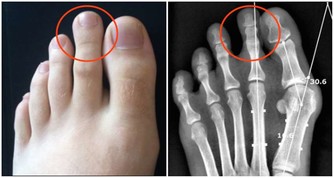

7.牙好就是腎好

牙齒也是說是跟骨頭一樣都是需要腎的精氣來養護,所以說你的腎氣充足的話,那麼牙齒就會十分的堅固,

口腔疾病就不會找上門來,反之就是出現牙齒鬆動甚至是脫落的情況。